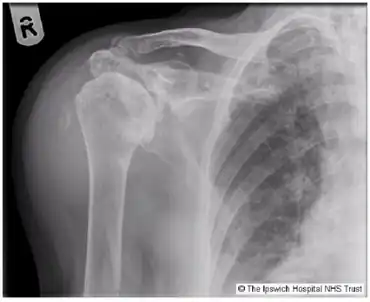

| Milwaukee shoulder syndrome X-ray. | |

Milwaukee shoulder syndrome (MSS) (apatite-associated destructive arthritis/Basic calcium phosphate (BCP) crystal arthritis/rapid destructive arthritis of the shoulder[1] is a rare[2] rheumatological condition similar to pseudogout, associated with periarticular or intra-articular deposition of hydroxyapatite or basic calcium phosphate (BCP) crystals. While primarily associated with the shoulder joint, it can affect any joint in the body below the head.[3] Along with symptomatology, the disease typically presents with positive radiologic findings, often showing marked erosion of the humeral head, cartilage, capsule, and bursae. Though rare, it is most often seen in females beginning in their 50s or 60s. Patients often have a history of joint trauma or overuse, calcium pyrophosphate dehydrate crystal deposition, neuroarthropathy, dialysis-related arthropathy or denervation.[2]